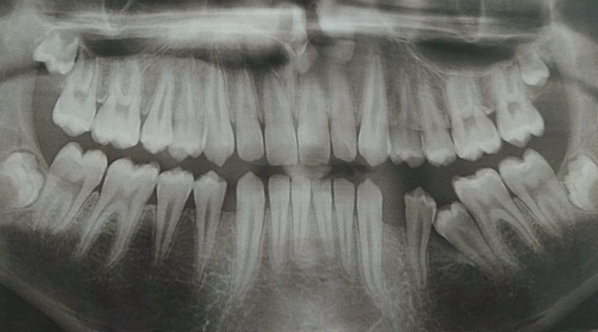

У моего ребенка выпали зубы передние верхние уже как 2,5 года. Новые зубы не растут. Один зуб вылез и тот поперек и на половину, и остановился в росте.

Ребенку уже 12 лет, а он без зубов. Снимок делали, зубы есть. Все остальные зубы вылезли один за другим, а вот с передними проблема.

Рекомендуем вам обратиться к стоматологу-ортодонту. В ряде случаев встречается анкилоз зуба или что либо, блокирующее прорезывание. Причину лучше искать на КЛКТ.